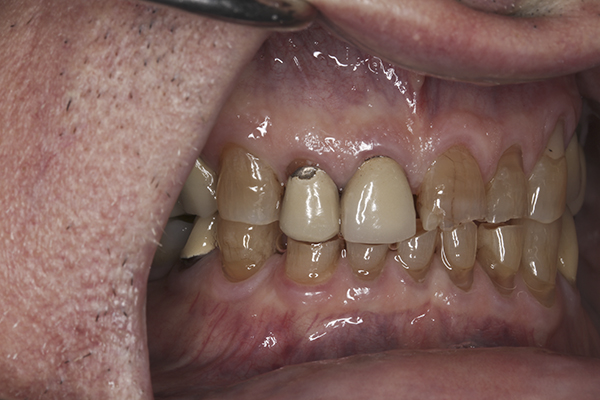

(12.) Preoperative right anterior, close-up view.

Figure 12